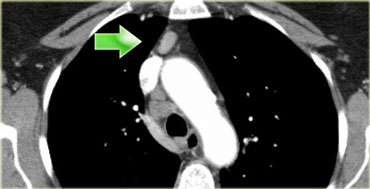

On the left we see 4R paratracheal nodes.

In addition there is an aortic node lateral to the aortic arch, i.e. station 6 node.